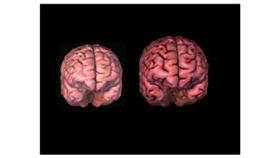

إذا قمنا بوزن دماغ رجل ودماغ امرأة سنجد أن دماغ الرجل أثقل بنسبة لا تقل عن 10 بالمئة وقد تصل إلى 20 بالمئة أحياناً، وهذا اختلاف يُضاف للاختلافات الكثيرة بين الرجل والمرأة.

وحتى نسبة موت الخلايا في الدماغ تختلف من الرجل إلى المرأة، وطريقة عمل هذه الخلايا تختلف، فقد وجد الباحثون أن نسبة انكماش الدماغ (تنكس الخلايا) عند الرجل أكبر منه وأكثر وضوحاً من المرأة مع تقدم العمر. وهكذا اختلاف في كل شيء تقريباً.